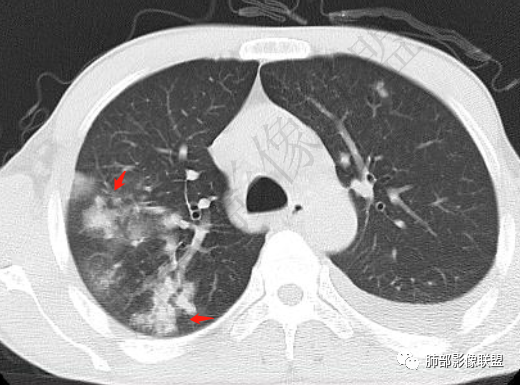

双肺多发大小不等结节影,边缘伴有磨玻璃影,边界欠清,部分与血管束相连,支气管似有穿行病灶内,结节有融合,左肺下叶厚壁空洞,伴有反晕征,左侧胸水,临床中年男性,发热40℃,CRP增高,感染性病变,1:类鼻疽伯克霍尔德菌(好发海南,影像表现也符合)

两肺多发斑片状实变影,周围GGO

主体还是沿支气管,大片叶段性分布

单凭影像:鹦鹉热、军团要考虑,因为内部无坏死,非典型气道为主

我纠结的是,这是气道来源还是血播,如果血播加上海南下田,优先类鼻疽,如果气道,军团也要考虑,只是没见过军团反晕,除非免疫缺陷,混合感染。另外肺克,肺克好像气血皆可,后面反晕出洞,如果没有海南,也要考虑吧,肺克也是免疫妥协相关菌

这一类表现等于是病灶没有沿气道趋势,不支持以肺实质、支气管的分布区域,我认为是沿气道到播散,间质蔓延为主

觉得后面那些符合血道,左下的更符合气道的